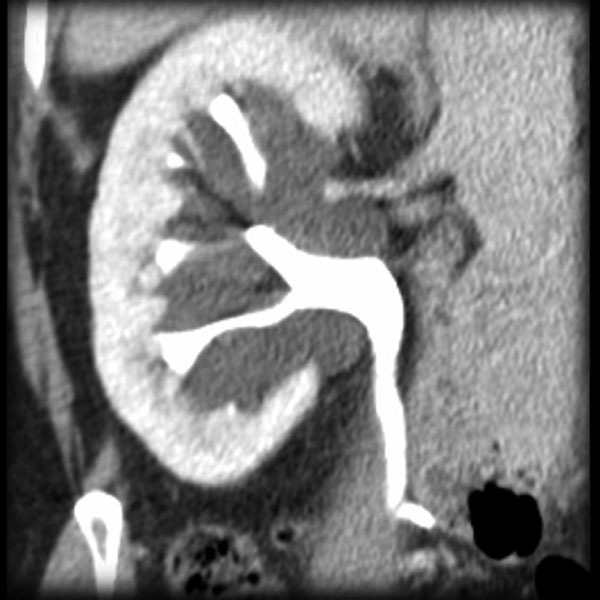

Case Discussion

Left sided duplicated collecting system with the upper moiety obstruction, and non-functioning. It displaces the lower pole moiety inferiorly, mimicking the appearance of a drooping lily.

The drooping lily sign refers to the inferolateral displacement of the opacified lower pole moiety due to an obstructed (and unopacified) upper pole moiety in duplicated collecting system.

Case courtesy of Dr Mohammad Taghi Niknejad, Radiopaedia.org, rID: 54354